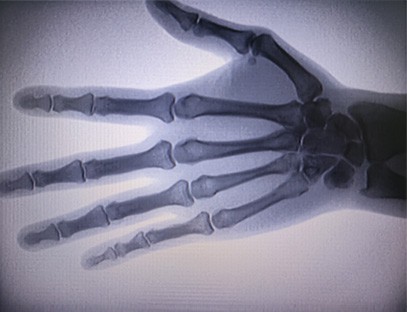

Una màquina de raigs X portàtilés un instrument portàtil de baixa dosi de radiació i molt segur que pot obtenir imatges d'alta qualitat alhora que redueix l'exposició a la radiació. Compensa les deficiències dels grans equips hospitalaris i es pot moure i transportar en qualsevol moment. Especialment indicat per a unitats i particulars amb pressupost insuficient i requeriments baixos d'imatges. La nostra màquina de raigs X de nova generació està equipada amb una pantalla gran d'alta definició de 10 polzades, que té un rang d'angle de visió més gran i pot veure completament a través de tota la palma, incloses fractures, luxacions, artritis i tumors ossis. Es pot connectar a una impressora de pel·lícules per imprimir pel·lícules ortopèdiques i també es pot utilitzar per a la producció i proves industrials. No cal una cambra fosca, perspectiva directa, observació en temps real. Aquesta màquina té un sistema d'imatge d'alta resolució que pot capturar imatges de qualsevol estructura òssia de manera molt clara. Proporcionar els millors equips i solucions de proves de raigs X per a fabricants de productes mèdics, mascotes, industrials, electrònics, departaments d'inspecció i manteniment i laboratoris d'investigació.

Especialització:Dissenyat per a les necessitats de les clíniques ortopèdiques, especialment indicat perImatge de raigs Xd'extremitats com mans, canells, colzes, espatlles, genolls, turmells, etc.

Imatge clara:La tecnologia d'imatge digital avançada s'utilitza per proporcionar imatges de raigs X d'alta qualitat, ajudant els metges a diagnosticar la malaltia amb precisió.